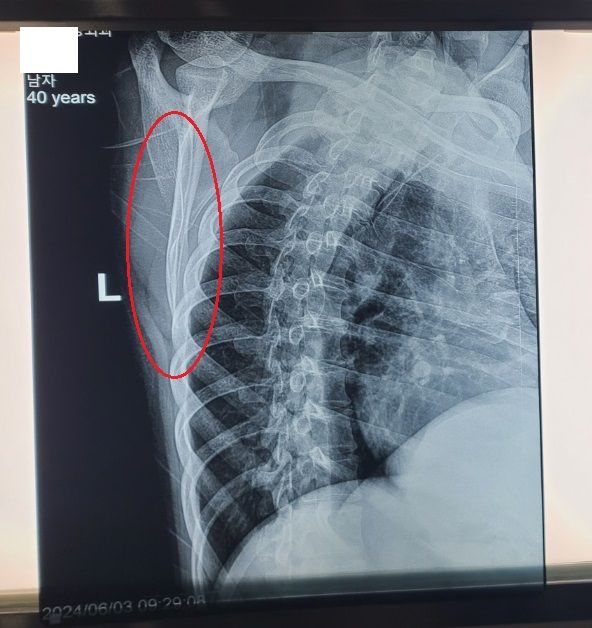

등 신경이 손상되었을 경우에는 수술을 받아야 하나요?

2주전에 회사동료와 장난을 치다가 동료의 주먹에 왼쪽 등부위를 약하게 맞았는데,

그게 살짝 아프기 시작하더니, 아직도 아픈 상태입니다.

병원에서는 경미한 근육파열이라고 하는데, 경미한게 물리치료를 2번이나 받고 약을 먹고 있는데도,

아직도 아픈걸 보니까 경미한게 아닌 것 같아요ㅠㅠ

병원에서 전기치료기를 통해서 치료를 받을 때 강도를 다소 쎄게 했고, 시중에 파는 마사지기로

다친 부위를 다소 강하게 마사지 하였는데, 그 영향으로 등 신경이 손상되지 않았나 싶습니다.

• 1번 째 사진